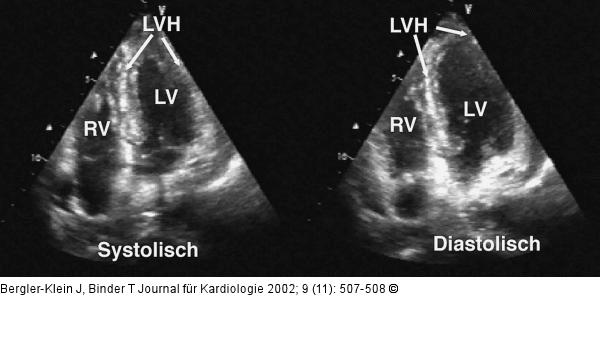

Abbildung 2: Metastasiertes Melanom - Kardiale Manifestation Vierkammerblick in Systole und Diastole: deutliche Hypertrophie (LVH) und inhomogene Echogenität des Septums. LV = linker Ventrikel, RV = rechter Ventrikel. |

Vierkammerblick in Systole und Diastole: deutliche Hypertrophie (LVH) und inhomogene Echogenität des Septums. LV = linker Ventrikel, RV = rechter Ventrikel. |